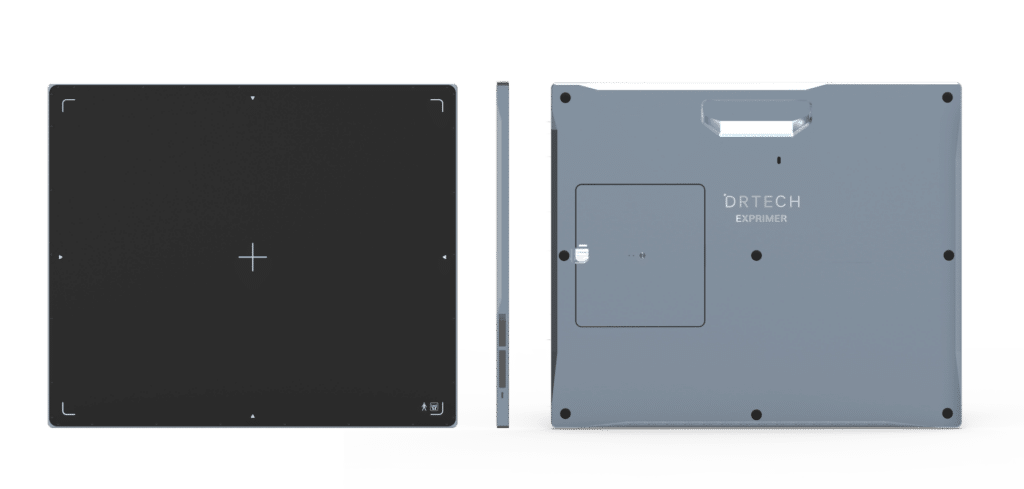

EVS W Series

Next Generation DR

EVS W DR Panels can be used in a variety of veterinary applications and environments. Their robust design enables detailed imaging even in challenging environments.

- 10″ x 12″, 14″x17″, 17″ x 17″ sizes

- Lightweight unibody housing

- IP56 liquid ingress protection rating

- Multi-antenna wireless connectivity

EVS W Series

Next Generation DR

All Day Performance

Whether in an exam room or in an equine stable, EVS W DR Panels Series are designed to optimize your Veterinary DR performance all day, every day

- Lightweight, but robust enough for remote imaging

- Image in stables all day with 2 included batteries

- Protect data by storing up to 200 images on the panel

- OLED window clearly displays critical panel status

Strong, yet Light

EVS W DR Panels Series utilize strong, resilient carbon fiber to yield panels that are much lighter in weight than traditional film cassettes, yet have a weight capacity of 300+ pounds.

IP56 Protection

IP56 compliant construction makes EVS W DR Panels Series water-resistant. So, they can tolerate splashes and disinfectant routines and remain fully operational.